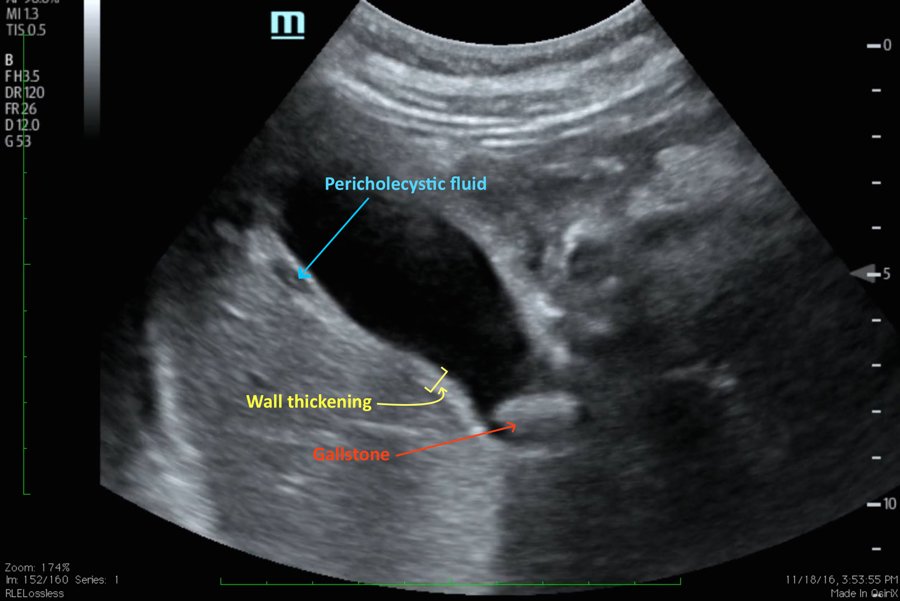

A 46-year-old female with a history of an aortic arch repair secondary to invasive aspergillosis in addition to a known history of gallstones presented to the emergency department with two days of right upper quadrant pain, fever, nausea and vomiting.

The patient’s vital signs were significant for tachycardia. Physical exam was notable for a positive Murphy’s sign. Initial labs were significant for leukocytosis with an elevated alkaline phosphatase. Bedside point-of-care ultrasound revealed a distended gallbladder, thickened gallbladder wall, pericholecystic fluid, and a stone in the neck of the gallbladder indicative of acute cholecystitis.

In this case, the patient was deemed a poor surgical candidate given her history of invasive aspergillosis and previous aortic arch repair; thus the patient underwent cholecystostomy tube placement by interventional radiology. On insertion of the cholecystostomy tube, frank purulent material was drained.